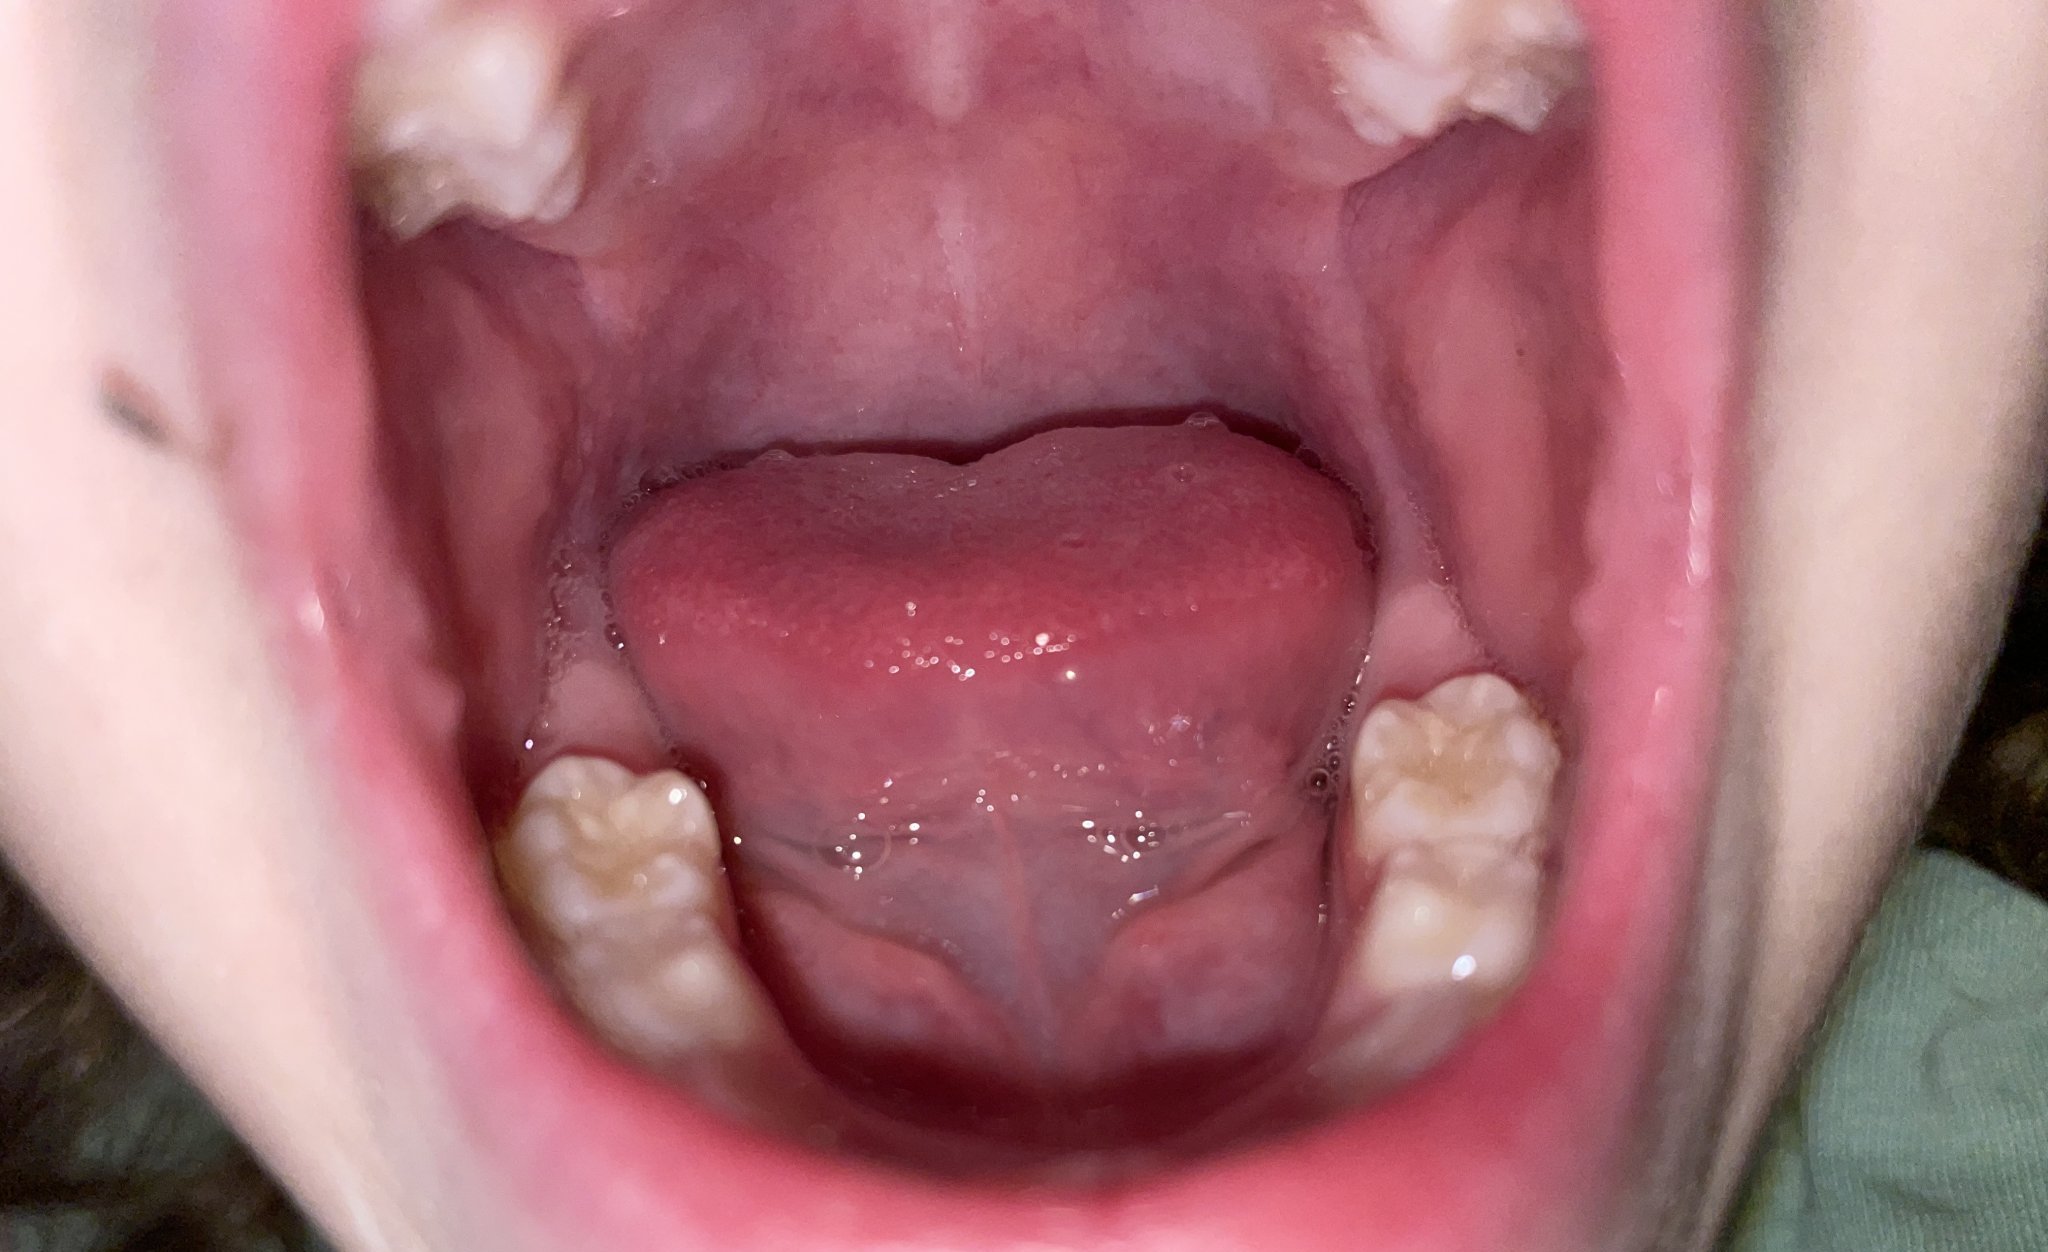

Здравейте, на дъщеря ми (3г и половина) забелязах мин. Седмица че има жълти петна по дъвкателната част на кътниците. Мие зъбки всеки ден с моя помощ, не е остатък от храна, притеснява ме дали не е зачатък на кариес. След празниците мисля да я заведа на зъболекар, но със сигурност ще чакам поне месец за час.

Дори, не са кариеси. Simple Smile Все пак посетете стоматолог, един профилактичен преглед никога не е излишен. Simple Smile